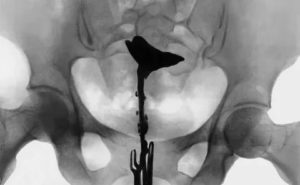

Метросальпингография

МСГ – это одна из современных диагностических процедур, позволяющих оценить проходимость маточных труб. В ходе ее проведения можно не только обнаружить спайки, но и удалить их. Они просто разбиваются раствором, который в придатки подается под напором.

Подготовка к процедуре сводится к сдаче мазка из влагалища на анализ. Также потребуется провести клиническое исследование крови. Контроль МСГ осуществляется с помощью рентгенологического аппарата.

Катетер вводят в полость матки и приближают его максимально близко к придаткам. Это позволит снизить влияние раствора на саму маточную полость.

Когда трубы будут заполнены, врач выполнит серию рентгенологических снимков.